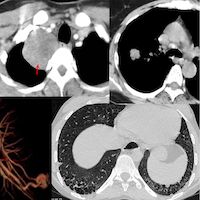

55-yrs old with myasthenia and chest radiograph showing bilateral paracardiac fat pads - traditionally called epicardial fat pads.

The video describes these fat pads, why they appear the way they do on radiographs and the correct terminology - epicardial vs pericardial adipose tissue vs fat pads.